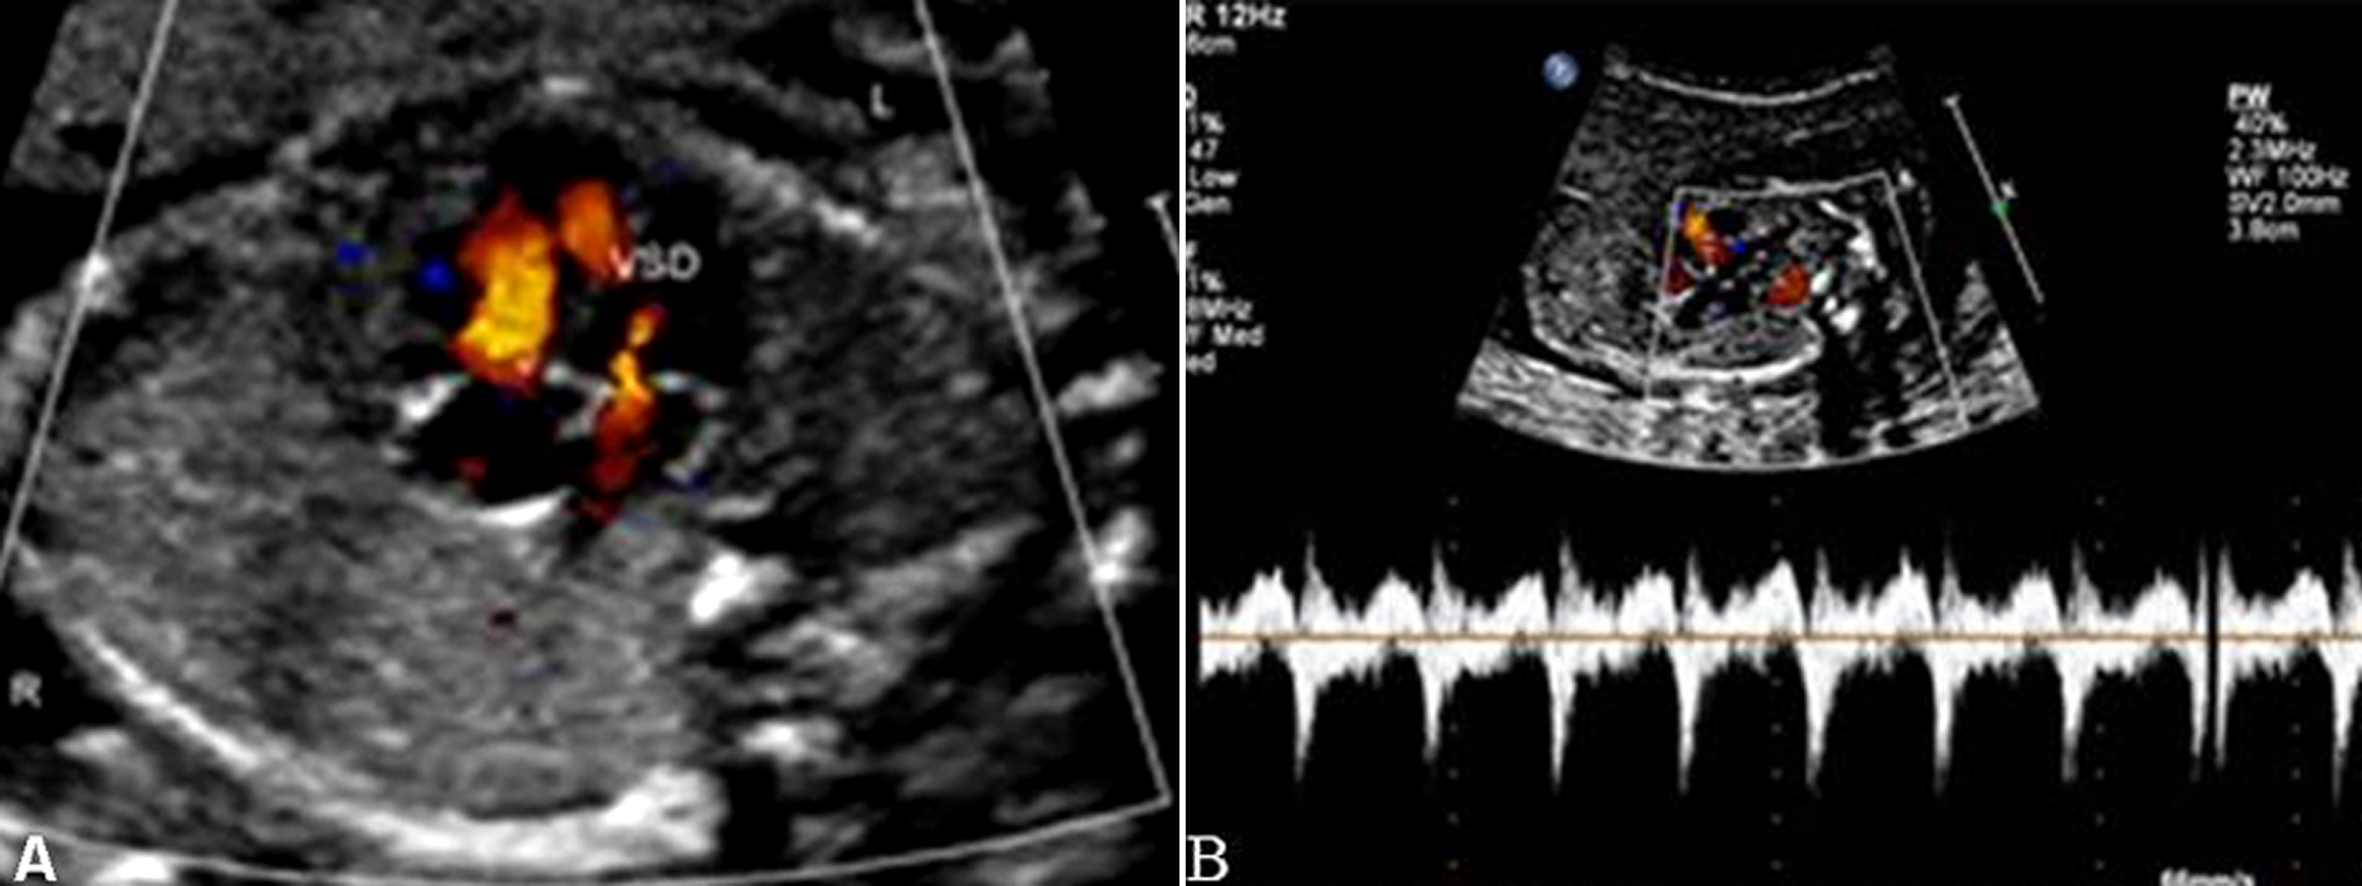

一般5mm以内的VSD在胎儿期容易被漏诊。漏诊原因不仅是由于缺损太小,而且还与是否有室间隔穿隔血流的存在有关。在心尖四腔心切面观,室间隔回声与声束平行,由于超声的侧壁失落效应易使膜部室间隔发生回声失落,出现缺损的假象,此时需改变探头角度以获得胸骨旁四腔心切面观,使得室间隔与声束垂直以观察室间隔的连续性,同时应用彩色多普勒观察是否有穿隔血流,还可应用多普勒时间流速曲线测量穿隔血流以进一步证实。因此有穿隔血流存在是胎内诊断VSD的可靠指标(图1、图2)。

图2 胎儿肌部室间隔缺损 A:肌部室间隔中断处见穿隔血流;B:在室间隔中断处测及双向血流时间流速曲线